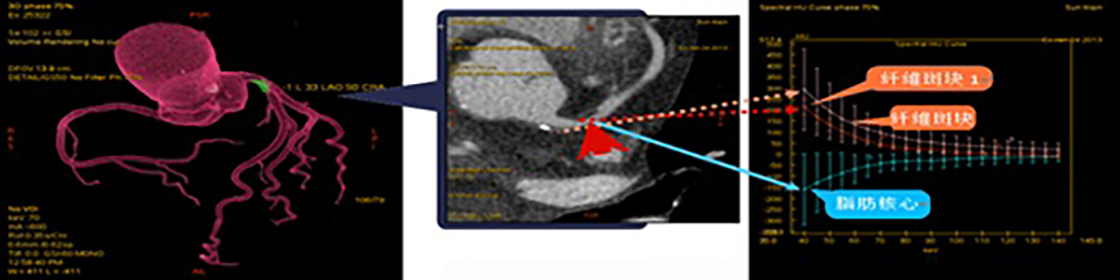

由于軟斑塊的危害程度在一(yī)定程度上高于鈣化斑塊,如CT檢查能增加了解軟斑塊的性質,對于斑塊的穩定性判斷及治療将有極大(dà)幫助。另外(wài)動态觀察軟斑塊性質變化可為病變愈後趨勢判斷提供一(yī)定的依據。實現此功能要求CT檢查在傳統的形态學成像基礎上增加組織或病變成份判斷的功能。因此對臨床醫學更有助益的應為心髒冠脈能譜成像,應用能譜掃描技術可以對冠脈斑塊成份性質進行分(fēn)析(圖4),預判斑塊的危險性或斑塊演變進程,為進一(yī)步治療提供信息。文獻介紹及目前國内一(yī)些醫院實際使用效果顯示能譜CT技術的發展已可以在自然心率下(xià)(無需控制心率)對心髒及冠脈進行常規成像和能譜成像,成為臨床應用覆蓋最廣的超高端CT。